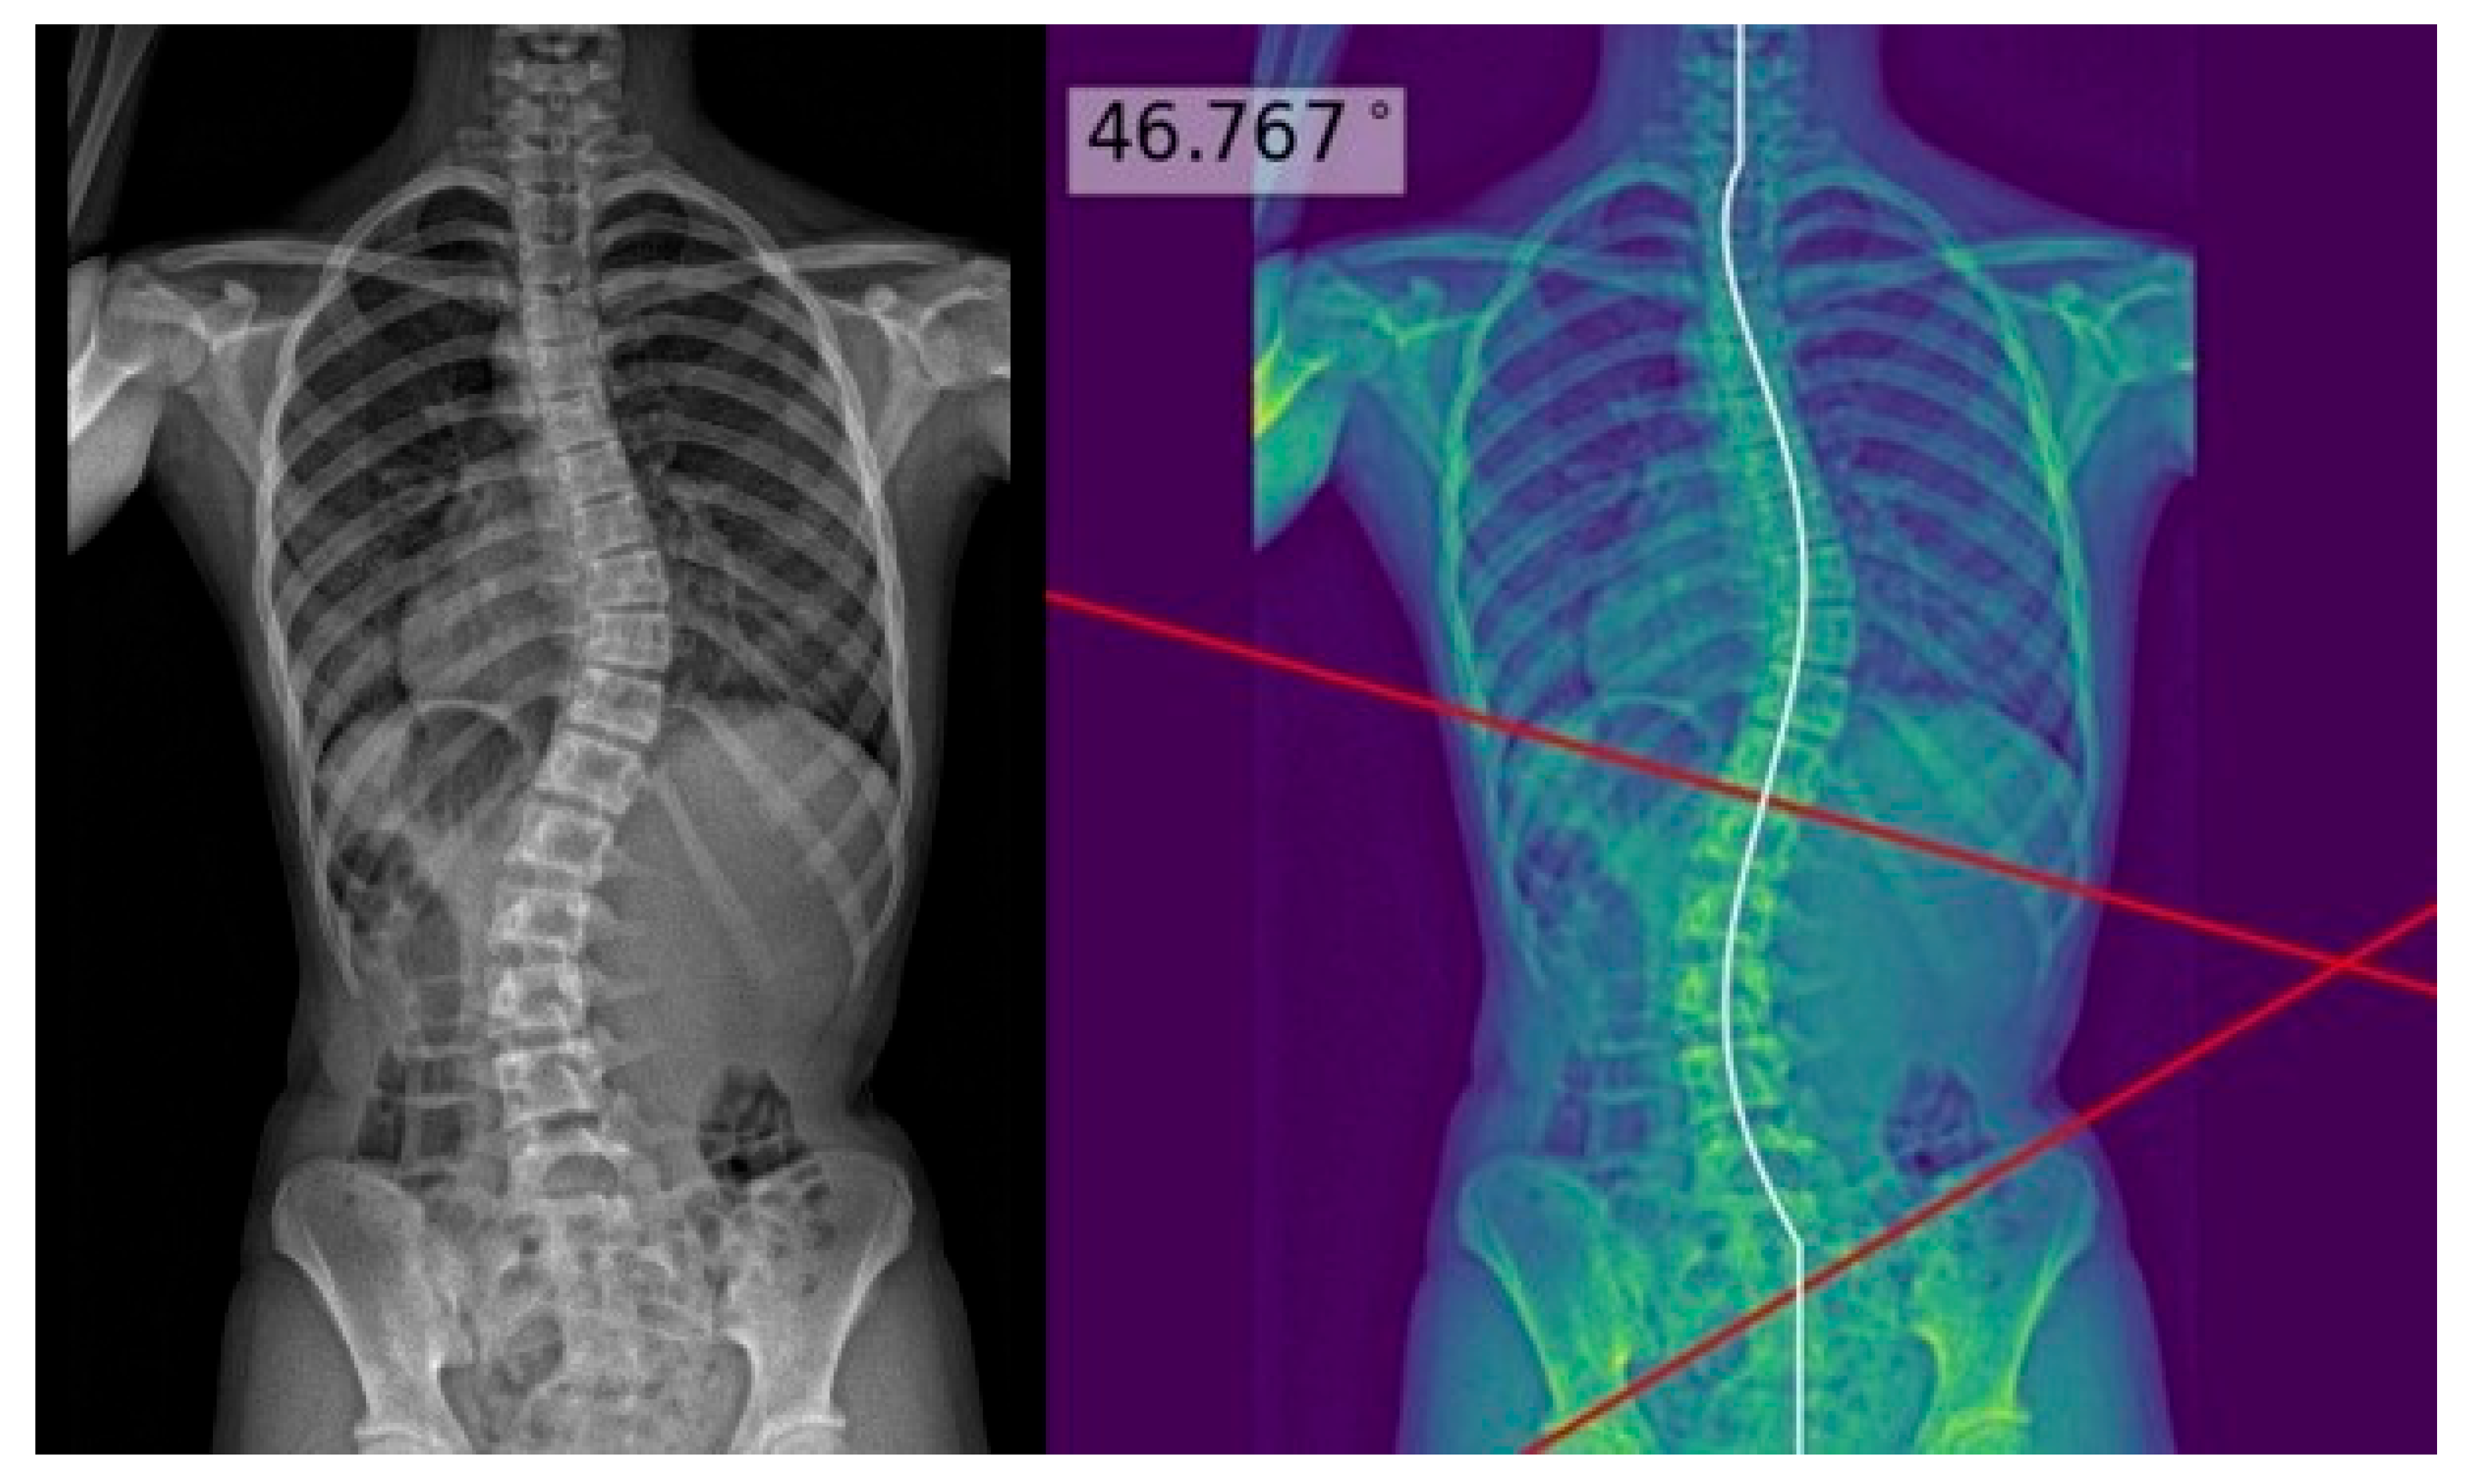

The process above allowed deep learning model masks of the whole spine (showing individual vertebrae) to be obtained and compared to the manual annotations. The model achieved a Dice similarity coefficient of 0.88 and Intersection over Union (IOU) of 84% on validation; it achieved a Dice coefficient of 0.619 and IOU of 72% on testing. Using the masks, the deep learning model determined the center of each vertebra, and extrapolated a polynomial curve along the centers. The spline technique, or the exhaustive assessment of the maximum angles between the vertebrae center line pairs to determine the largest angle, was the method of choice for the measurement of Cobb’s angle. Once the model has identified the correct points on the line, the reader could view the model prediction as extended lines and text in the top right hand corner of the image. For physicians’ review and augmentation, the model (available at the following web server: https://radweb.sha.endeavour-poc.ai/, accessed on 1 May 2022) annotated the largest possible angle in the output images, as shown in Figure 2 and Figure 3. Appendix A provides more details on the deep learning model.

The readers performed manual measurements of the major coronal curve angle without assistance from the deep learning model using the digital angle tool on the Picture Archiving and Communication System (PACS) (Centricity, GE Healthcare, Chicago, IL, USA), with the results overlaid on the images. When interpreting the radiographs with assistance from the deep learning model, the readers accessed the automated major coronal curve calculations and annotations overlaid on the images (as illustrated in Figure 2 and Figure 3). The readers could accept the model predictions or perform manual calculations using the same digital tool as per their clinical judgment, especially if the center curve alignment did not match the image.

Figure 2. Posteroanterior whole-spine radiograph for scoliosis assessment (left) with the deep learning model predictions overlaid on the processed image (right). The deep learning model extrapolated a polynomial curve along the centers of the vertebrae, and highlighted the predicted Cobb’s angle for the reader at the maximum angulated curve. This is an example of a good model prediction, with less than three degrees of difference from the reference standard.